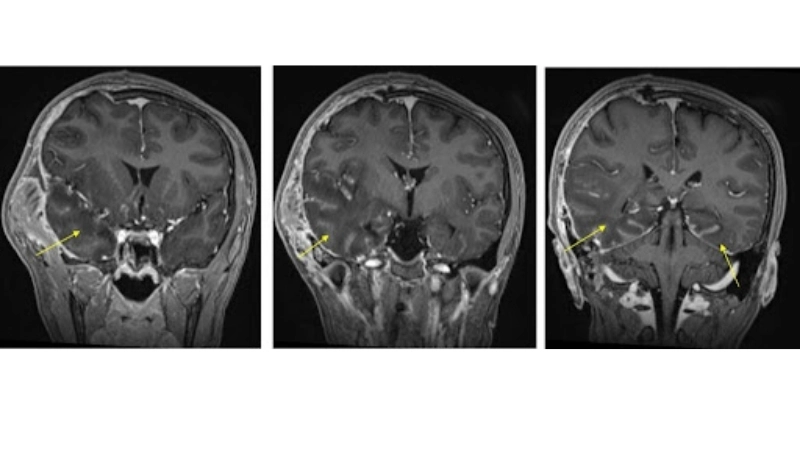

Image description of Herpes Simplex Encephalitis

Herpes Simplex Encephalitis is a rare but serious brain infection caused by herpes simplex virus. It leads to fever, headache, confusion, seizures, and potential long-term neurological damage. Early detection and treatment are crucial for recovery.

Encephalitis diagnosis needs MRI and lab tests